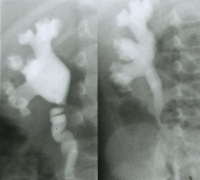

Als Beispiel die Ureterabgangsstenose bei multiplen Nierenbeckenkelchsteinen eines 2 Jahre alten Jungen (Abbildung HG2).